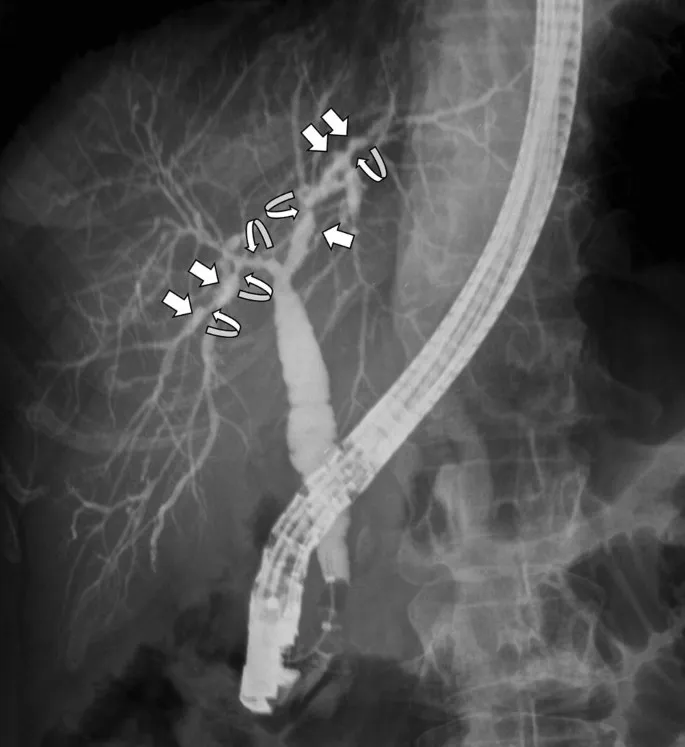

- Chronic inflammation, fibrosis, strictures of intra/extrahepatic bile ducts. "Beading".

- Patho: "Onion-skin" fibrosis. ERCP/MRCP: Multiple strictures, "Beads on a string".

- Lab: āALP, p-ANCA (+ve ~70%). High risk of cholangiocarcinoma (10-20%).